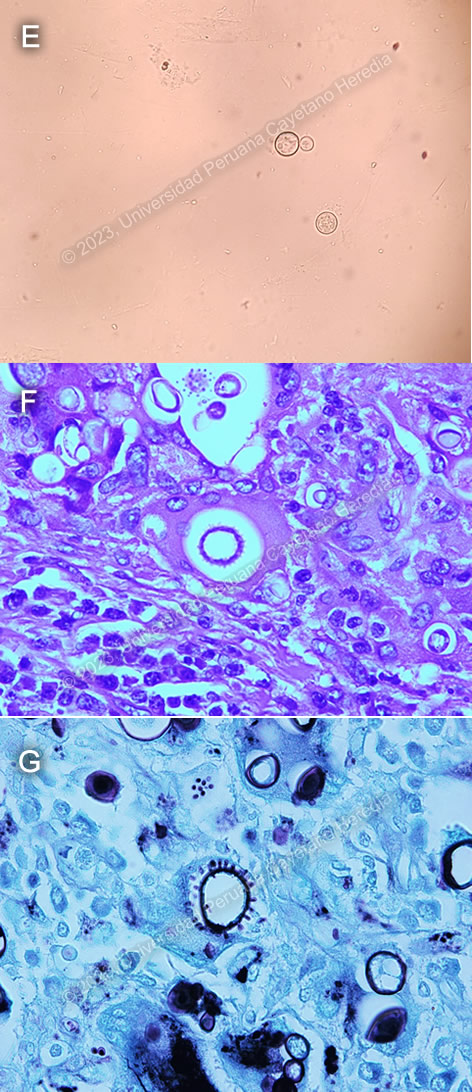

Discussion: A KOH of a sputum sample (Image E) showed large, oval, double walled cell with budding daughter cells, characteristic for Paracoccidioides spp. Histopathology of lymph node biopsy showed chronic granulomatous formations with yeast forms of varying sizes (5-30μm) in H&E staining (Image F), and a Grocott stain showing some of them with multiple peripheral budding in a “pilot wheel” pattern, suggestive of Paracoccidioides brasiliensis (Image G). Ziehl-Neelsen stains were negative for acid-fast bacilli.

Diagnosis usually relies on identification of Paracoccidioides spp in clinical or histopathological specimens. Typical forms include a mother yeast cell surrounded by budding daughter yeast cells in a “pilot wheel” pattern or surrounded by only two daughter buds in a “Mickey mouse head” pattern.